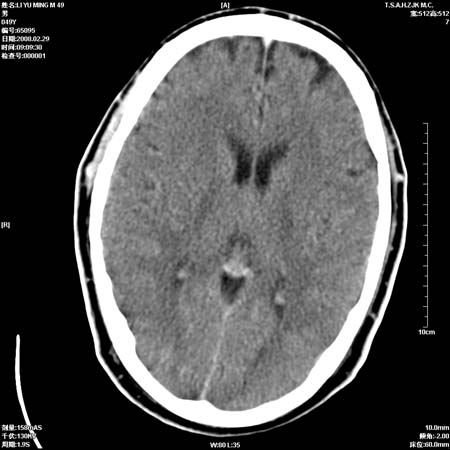

男性, 49岁, 头痛, 行ct检查后, 我科一名大夫报了蛛网膜下腔出血, 请大家讨论!

大脑纵裂池及鞍上池应该有蛛血

可能性脑动脉硬化所致

一周时间密度未见改变,考虑为正常图像(脑动脉硬化?)。